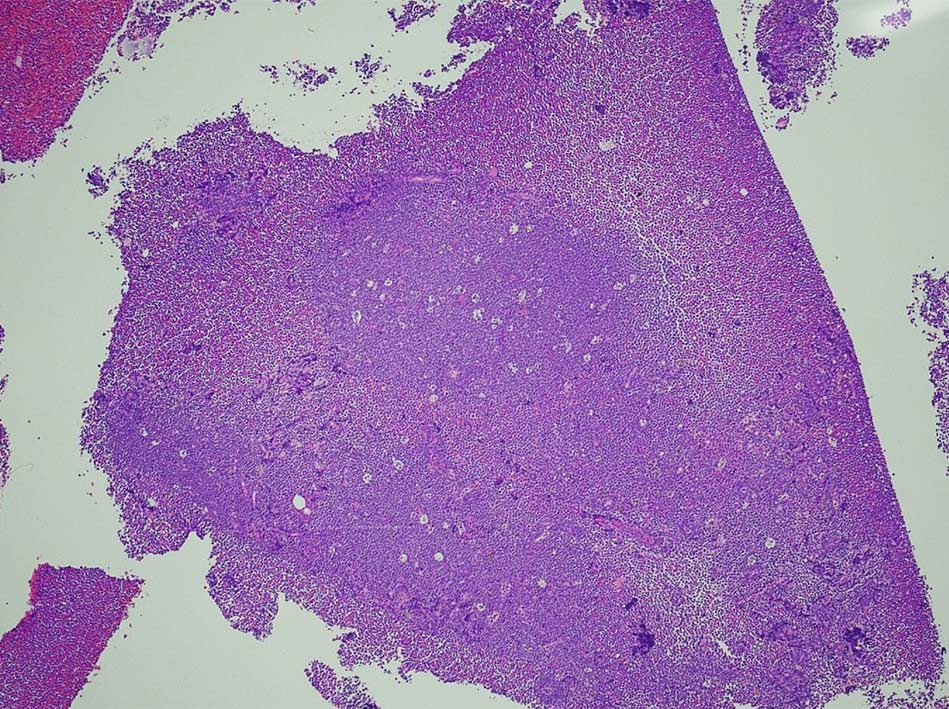

右肺上葉から前縦隔に90mm大の腫瘤あり. 右胸水貯留を伴う. 右主気管支より縦隔腫瘍のEBUS-TBNAをおこなう.

断片状組織片が採取され, 小型から中型の円形細胞がシート状密に増殖する. tindible body macrophagesが散在しstarry-sky様組織像を呈する組織片がある. CD3+, CD5+, CD20-, Ki-67 LI veru high(>95%),CD10-, BCL2(淡染だがほぼ100%膜陽性), BCL6陽性, MYC+(69%). T-cell neoplasmであるが, double expressorである. EBER-ISH陰性. CD4, CD8 double positive cellの増殖. CD25-, TIA1, granzymeBはいずれも陰性.